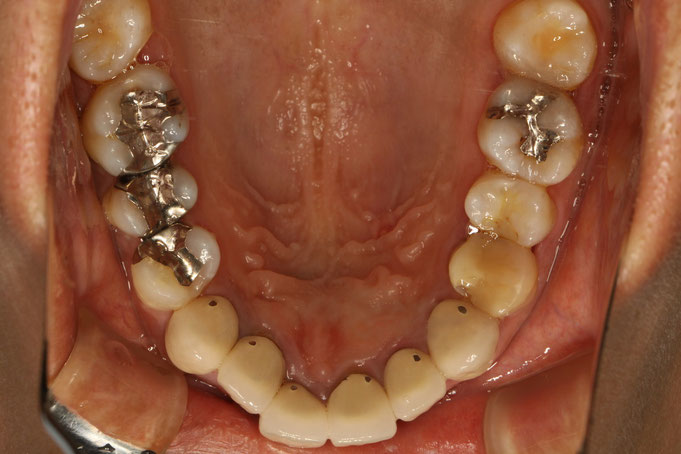

銀の詰め物を白くする審美歯科治療はセラミックインレーという方法で治療を行います。 審美歯科治療を行う際に、銀の小さい詰め物を白く場合があります。銀の詰め物の大きさによって呼び方が変わります。 歯の全周を削って被せるタイプの歯科技工物はクラウンと呼び、歯の一部奥歯の咬む面だけを削っていれるタイプはインレーと呼びます。奥歯のかむ面に十字型の金属なり補綴物が入っている場合は通常インレーです。